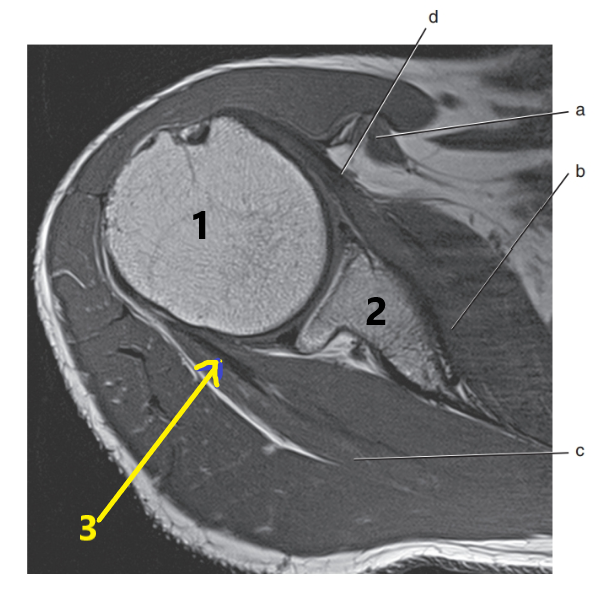

What is letter a?

Median nerve

Brachial artery

What is letter B pointing to ?

Humerus

What is arrow # 3 ?

Teres minor tendon